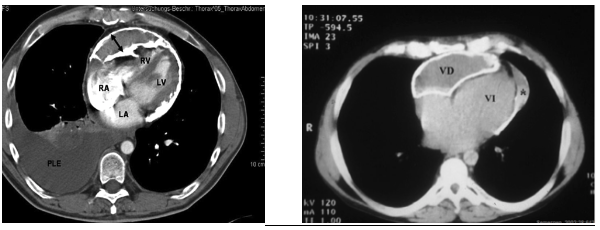

TAC: Es la técnica de elección para confirmar el diagnóstico, ya que no solo nos permite ver el pericardio, sino que en algunos casos de pericarditis podremos ver hasta si existen alteraciones de las arterias coronarias. Podremos ver afectaciones focales o generales del pericardio (lo normal es la alteración global).

El taponamiento afecta primero a las cavidades derechas (tienen menor presión)y a medida que se torna más severo, afecta también a la aurícula y ventrículo izquierdos. Una vez se sobrepasa el volumen de reserva de la cavidad pericárdica (15-50 ml), pequeños aumentos del volumen producen grandes aumentos de presión intrapericárdica, por lo que al drenarlo, con sacar pequeñas cantidades, conseguimos una gran bajada de presión y se alivian gravísimos taponamientos.